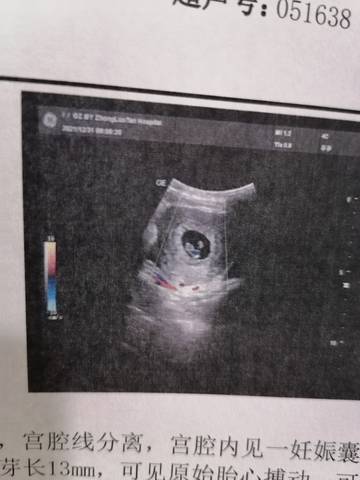

胚胎上面有个小白点,好好奇啊,医生没和我多说什么,应该没什么不妥,我就是纯纯好奇????

我觉得你不用太担心,这个情况下就是如果医生说没什么问题就属于正常现象,按时复查就可以了。

你好,做个小白点的话,没办法去帮你判断的呀,因为这次的话应该是没问题的啦,不要那么担心。